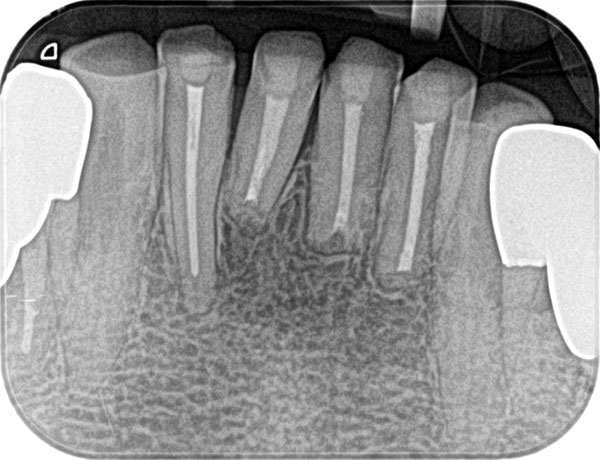

主訴: 噛むと痛い、左で食べれない。他の病院で神経が見つからない。根の先に病気がある。

通常だと手立てがなく、抜歯しかない歯も外科(根尖切除術)で治すことができます。

歯茎が腫れ、CT上では骨が大きくないことがわかります